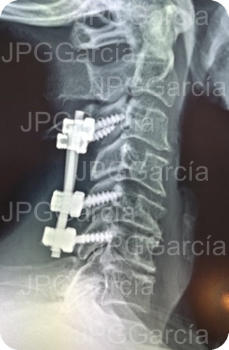

Instrumentación Cervical Posterior con tornillos y barras por Conducto Cervical Estrecho (vistas lateral y anteroposterior)

Radiografía lateral de cuello post quirúrgica la cual muestra la instrumentación cervical posterior colocada y una laminectomía cervical amplia para liberación del tejido medular